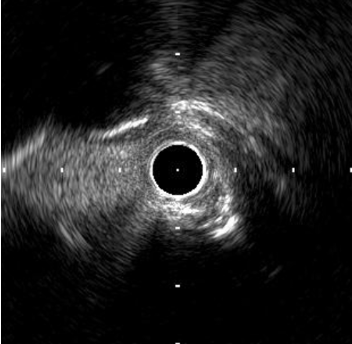

Rotational atherectomy with 1.25mm burr to LCxPoor expansion of NC balloon Further prepare lesion with shockwave 3.0.IVUS shows evidence of calcium fracture 3.0/15 stent deployed, followed by PSHP with NC 3.0 balloon Sion Blue redirected to LAD IVUS: concentric LM and pLAD calcification, 10 mm from mid LAD stent deployed 12 days ago

IVUS and angiogram show satisfactory stent expansion.